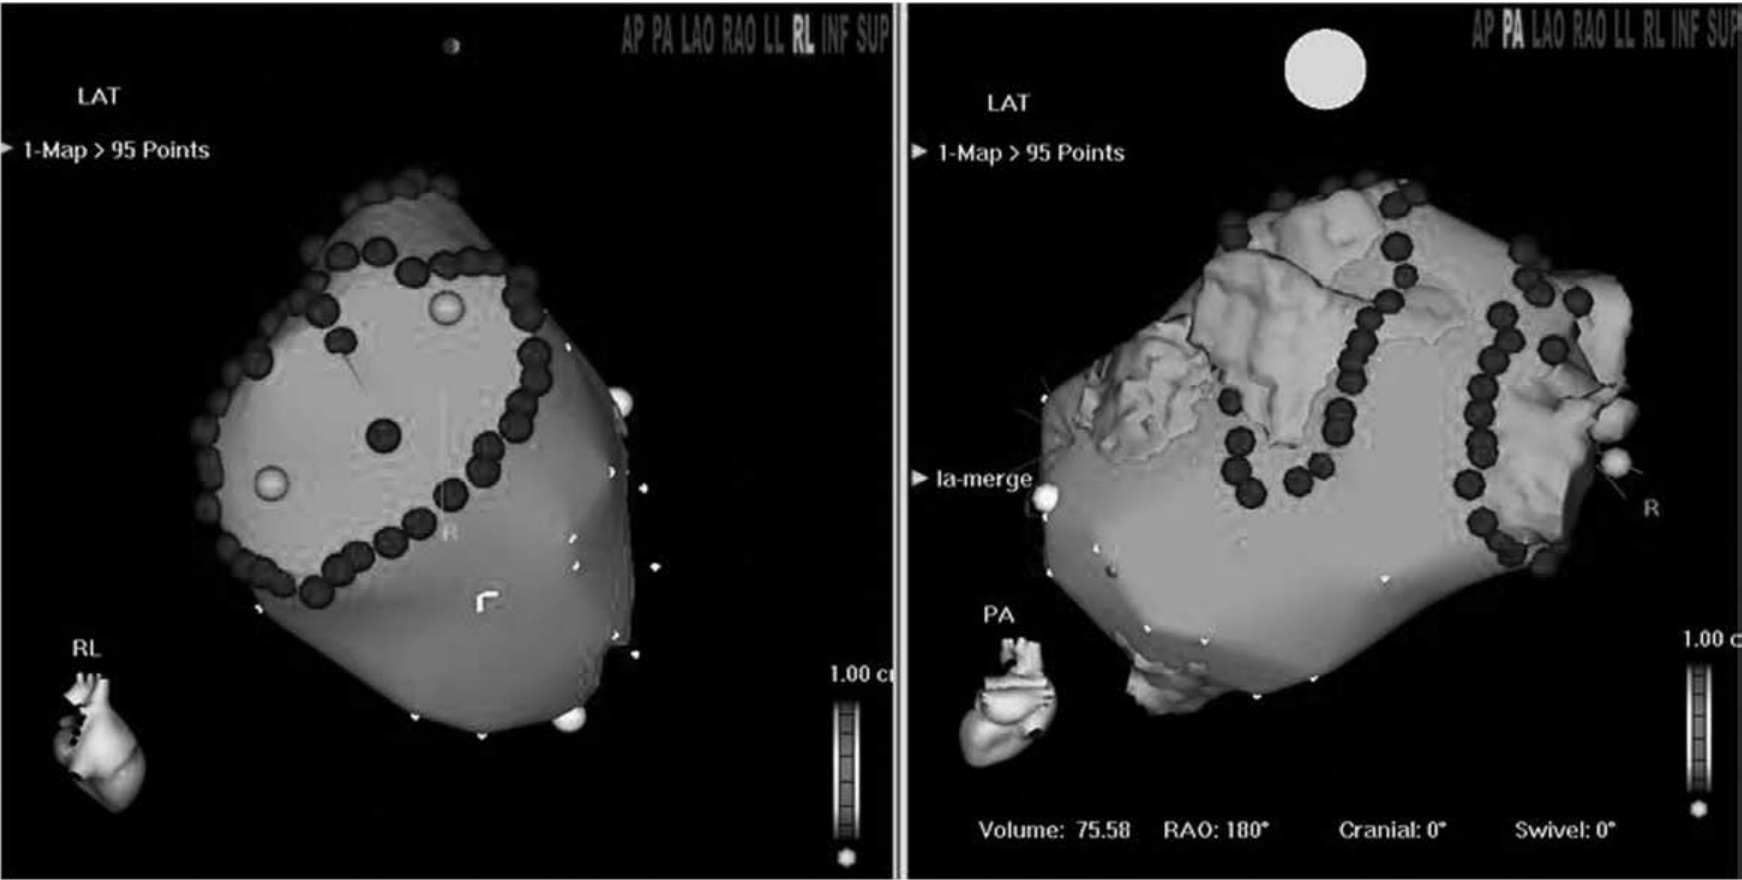

(2)环肺静脉线性消融(CPVA) 此种消融术式由Pappone于2000年首先创立。其原理是:在Carto三维电解剖标测系统的引导下,进行左心房三维重建,对双侧肺静脉前庭分别行大环状消融,以完全隔离肺静脉。目前,在许多电生理中心CPVA已经成为房颤的主要消融策略。CPVA治疗阵发性房颤的成功率一般接近90%,对持续性房颤的成功率为80%左右,对慢性房颤的消融成功率为68%左右。在CPVA的基础上可附加左心房顶部线、二尖瓣环峡部、三尖瓣环峡部的线性消融以提高房颤的治疗成功率(图64-13)。

图64-13 阵发性房颤的消融:在Carto三维电解剖标测系统的引导下,进行左心房三维重建,对双侧肺静脉前庭分别行大环状消融,以完全隔离肺静脉